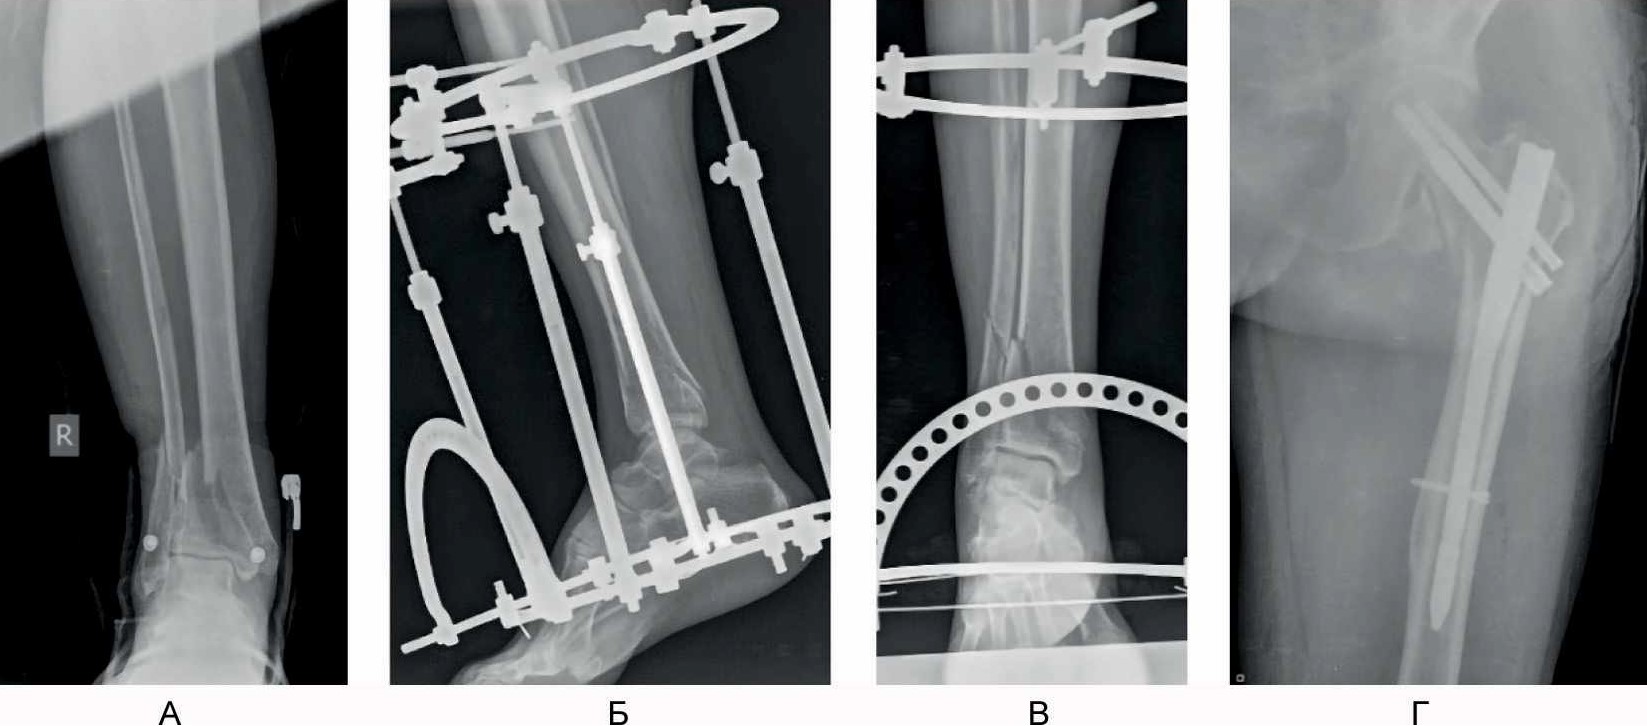

С учетом стабильного состояния пациента, в соответствии с протоколом лечения множественной и сочетанной травмы, пациент доставлен в операционную. Выполнена операция: закрытая репозиция, малоинвазивный остеосинтез левой бедренной кости проксимальным бедренным стержнем, внеочаговый остеосинтез правой голени аппаратом наружной фиксации с умеренной тракцией (рис. 1), первичная хирургическая обработка раны лба.

Рис. 1. Рентгенограммы пациента Б, 66 лет, в день поступления. А – первичная рентгенограмма голени и голеностопного сустава в прямой проекции; Б, В – первичная закрытая репозиция аппаратом наружной фиксации; Г – результат интрамедуллярного остеосинтеза перелома проксимального отдела бедренной кости.